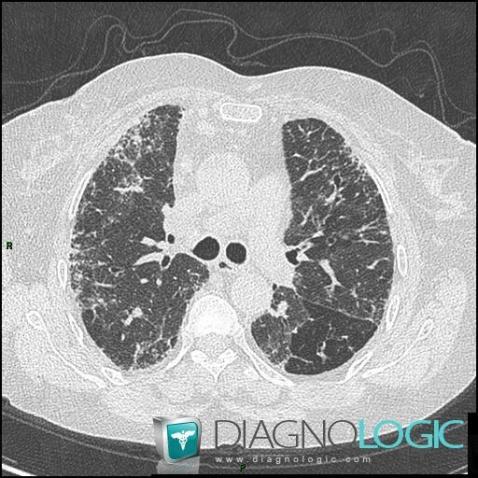

Mixed connective tissue disease, Pulmonary parenchyma, CT

Here is the specific information in the key image above:

- Diagnosis Mixed connective tissue disease, Location(s) Pulmonary parenchyma, with gamuts Peripheral and sub pleural zone disease, Pulmonary fibrosis